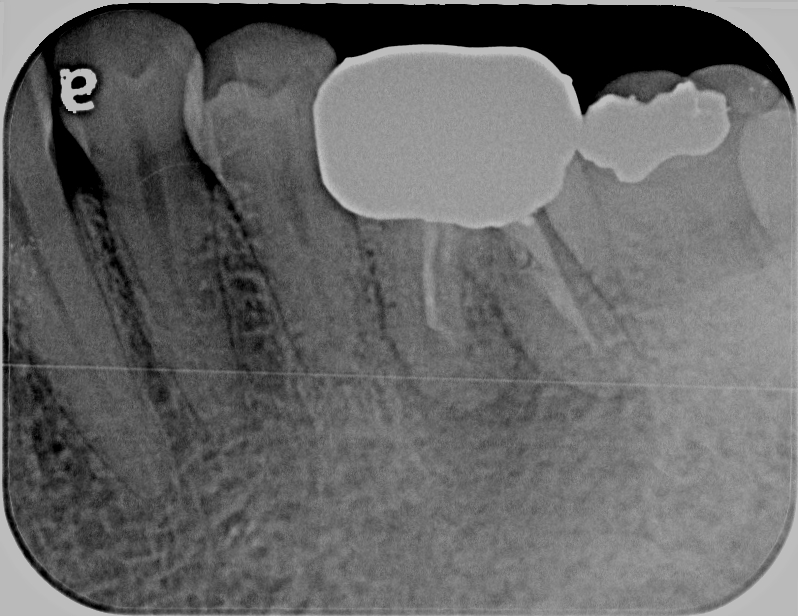

生駒郡在住 50代 女性 左下第一大臼歯 精密根管治療「腫れて痛い」

術前

診断:左下第一大臼歯 根尖性歯周炎

治療内容:ラバーダム使用 精密根管治療

治療時間:90分×2回

担当医のコメント:通常の根管治療と化学的洗浄を行い、1回目の治療で痛みはほぼなくなりました。

2回目で通常の根管充填剤とバイオセラミックシーラーで根管充填を行いました。3ヶ月経過、予後は良好です。